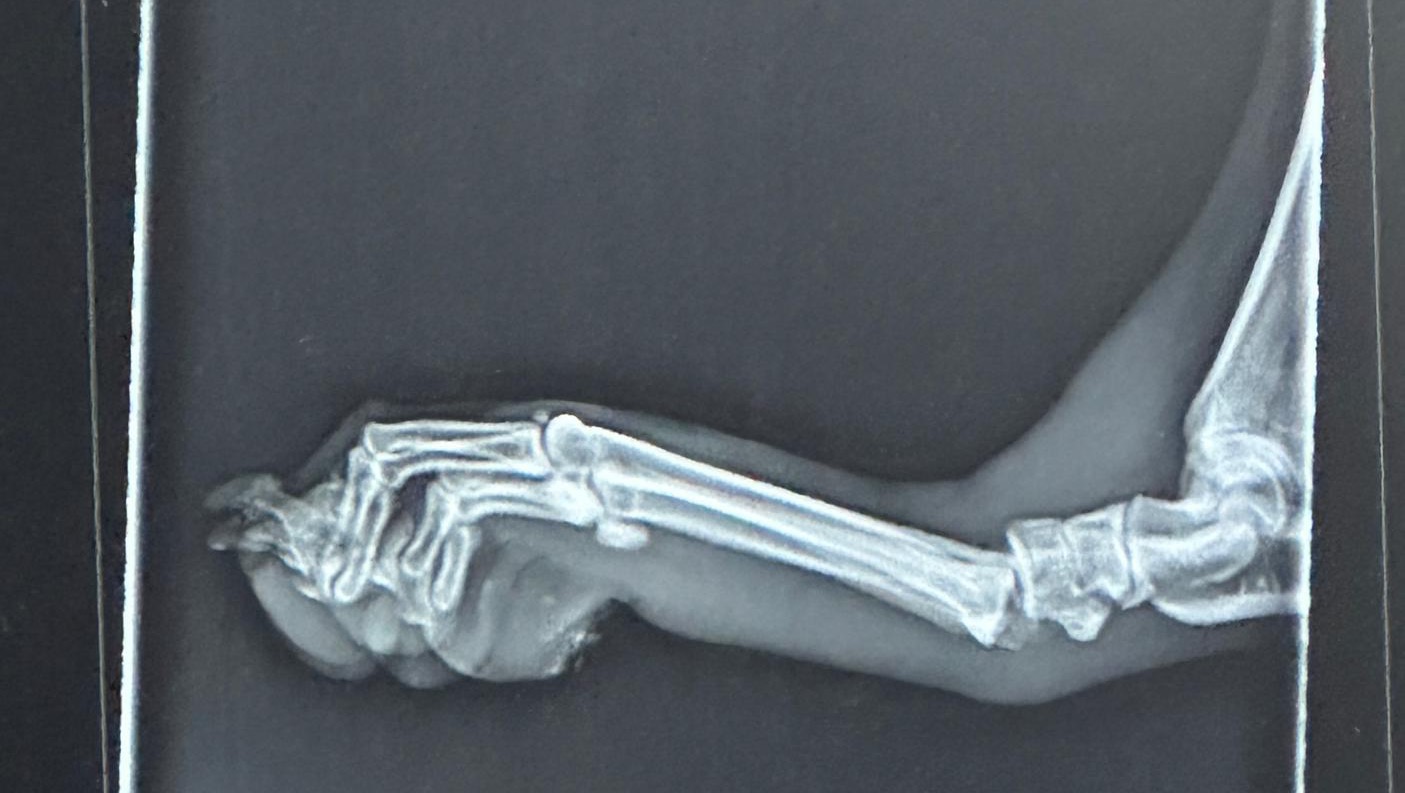

Unfortunately, over the weekend, Penelope suffered a devastating injury when she dislocated her toe. After seeing our trusted veterinarian, Dr. Gripp in Hico, TX, Penelope was referred to the expert team at I-20 Emergency Animal Hospital in Weatherford, TX.

It became clear that she needed specialized care, and she was ultimately sent to the renowned DVSC Orthopedic Surgeons in Fort Worth. They have recommended surgery and specialized post-surgery physical therapy to ensure a full recovery, which is estimated to cost around $13,800.